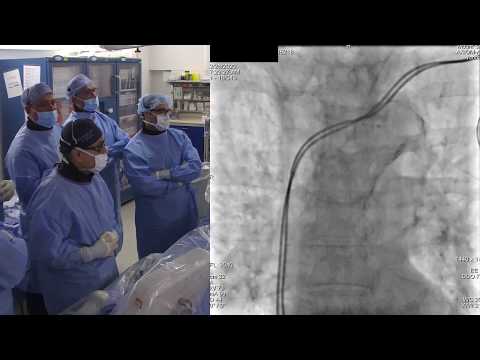

Endovascular Technique for Bilateral Ostial Iliac Disease with Distal Aortic Involvement D B Schn